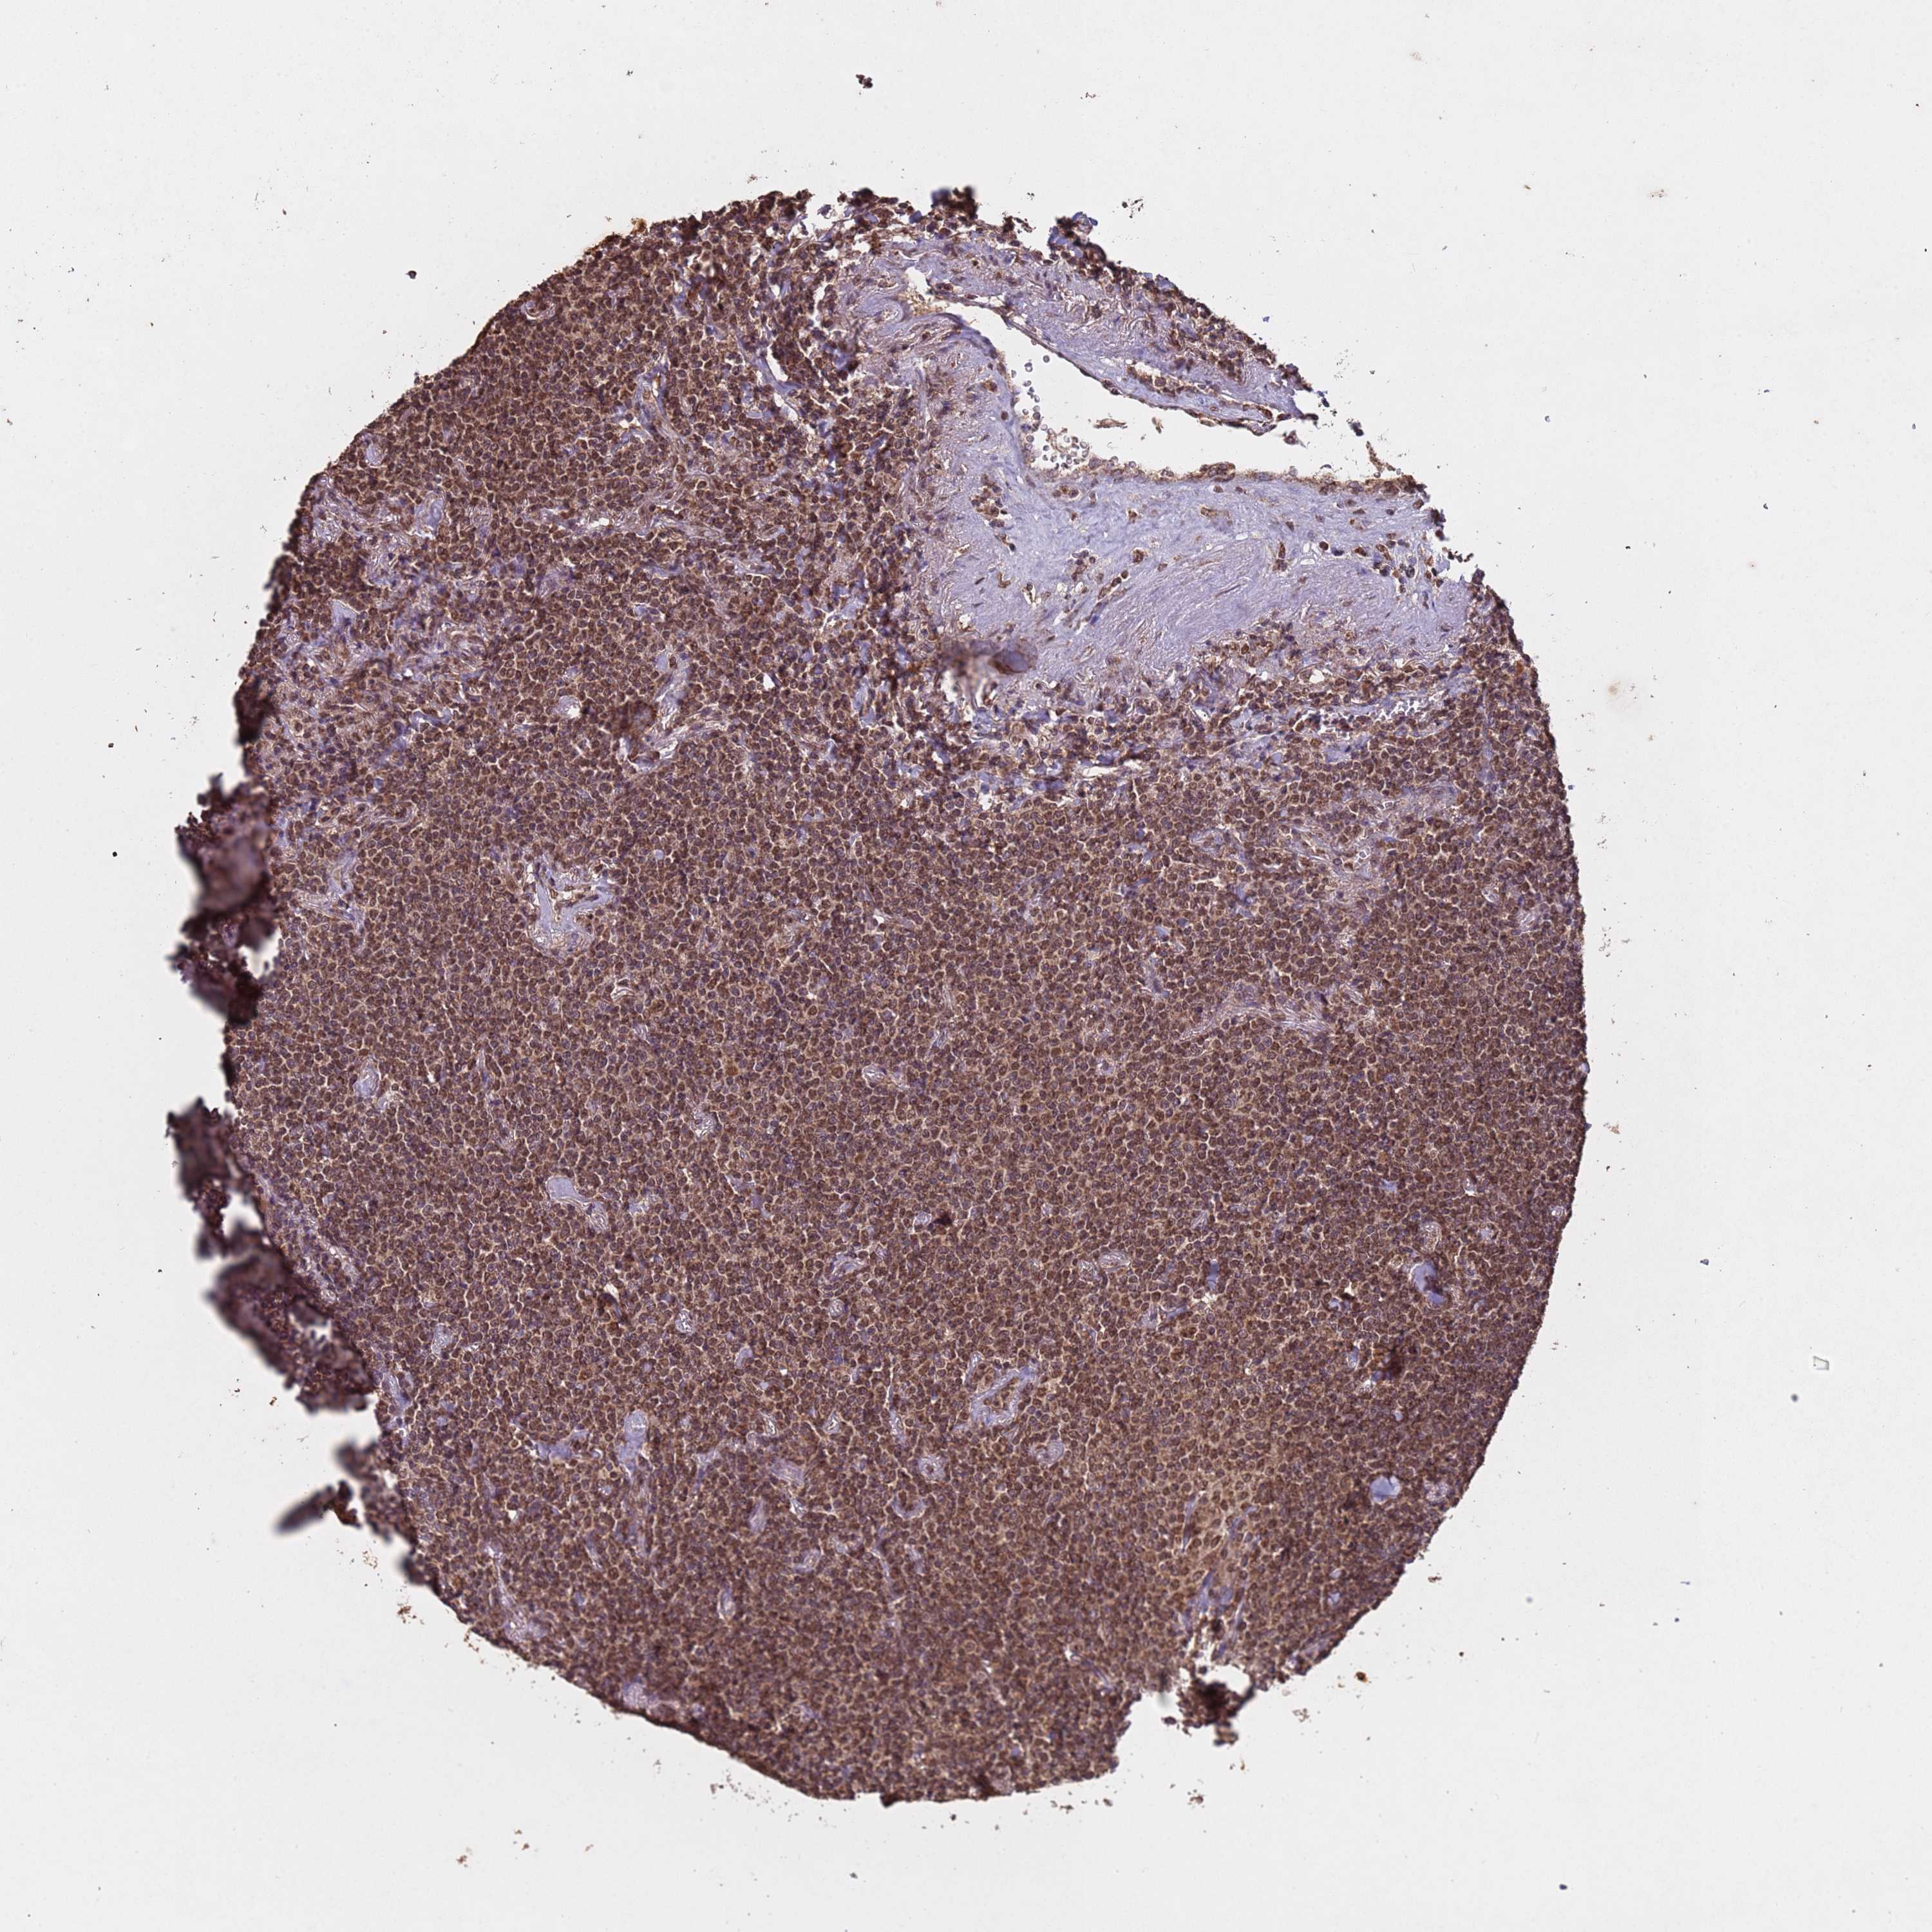

LYMPHOMA - Protein expressioni

A mouse-over function shows sample information and annotation data. Click on an image to view it in a full screen mode. Samples can be filtered based on level of antibody staining by selecting one or several of the following categories: high, medium, low and not detected. The assay and annotation is described here.

Antibody stainingi

Antibody staining in the annotated cell types in the current human tissue is reported as not detected, low, medium, or high, based on conventional immunohistochemistry profiling in selected tissues. This score is based on the combination of the staining intensity and fraction of stained cells.

Each image is clickable and will lead to virtual microscopy that enables deeper exploration of all samples and also displays staining intensity scores, fraction scores and subcellular localization as well as patient and tissue information for each sample.

Antibody CAB045977

Staining

High

Intensity

Strong

Location

Nuclear

Hodgkin's disease, NOS

Malignant lymphoma, non-Hodgkin's type, High grade

Malignant lymphoma, non-Hodgkin's type, Low grade